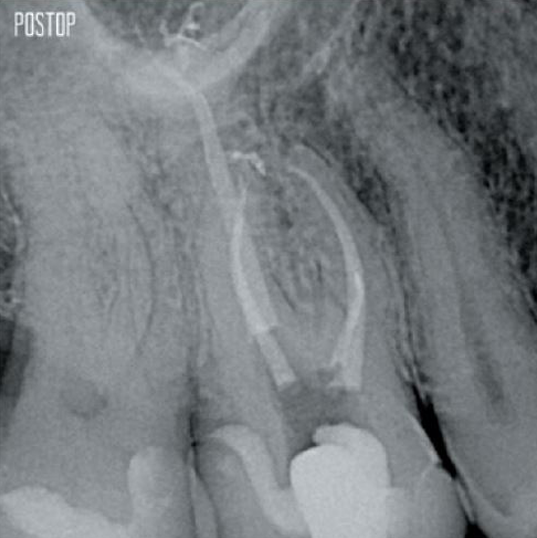

Fotos cortesía del Dr. Ahmed Salman